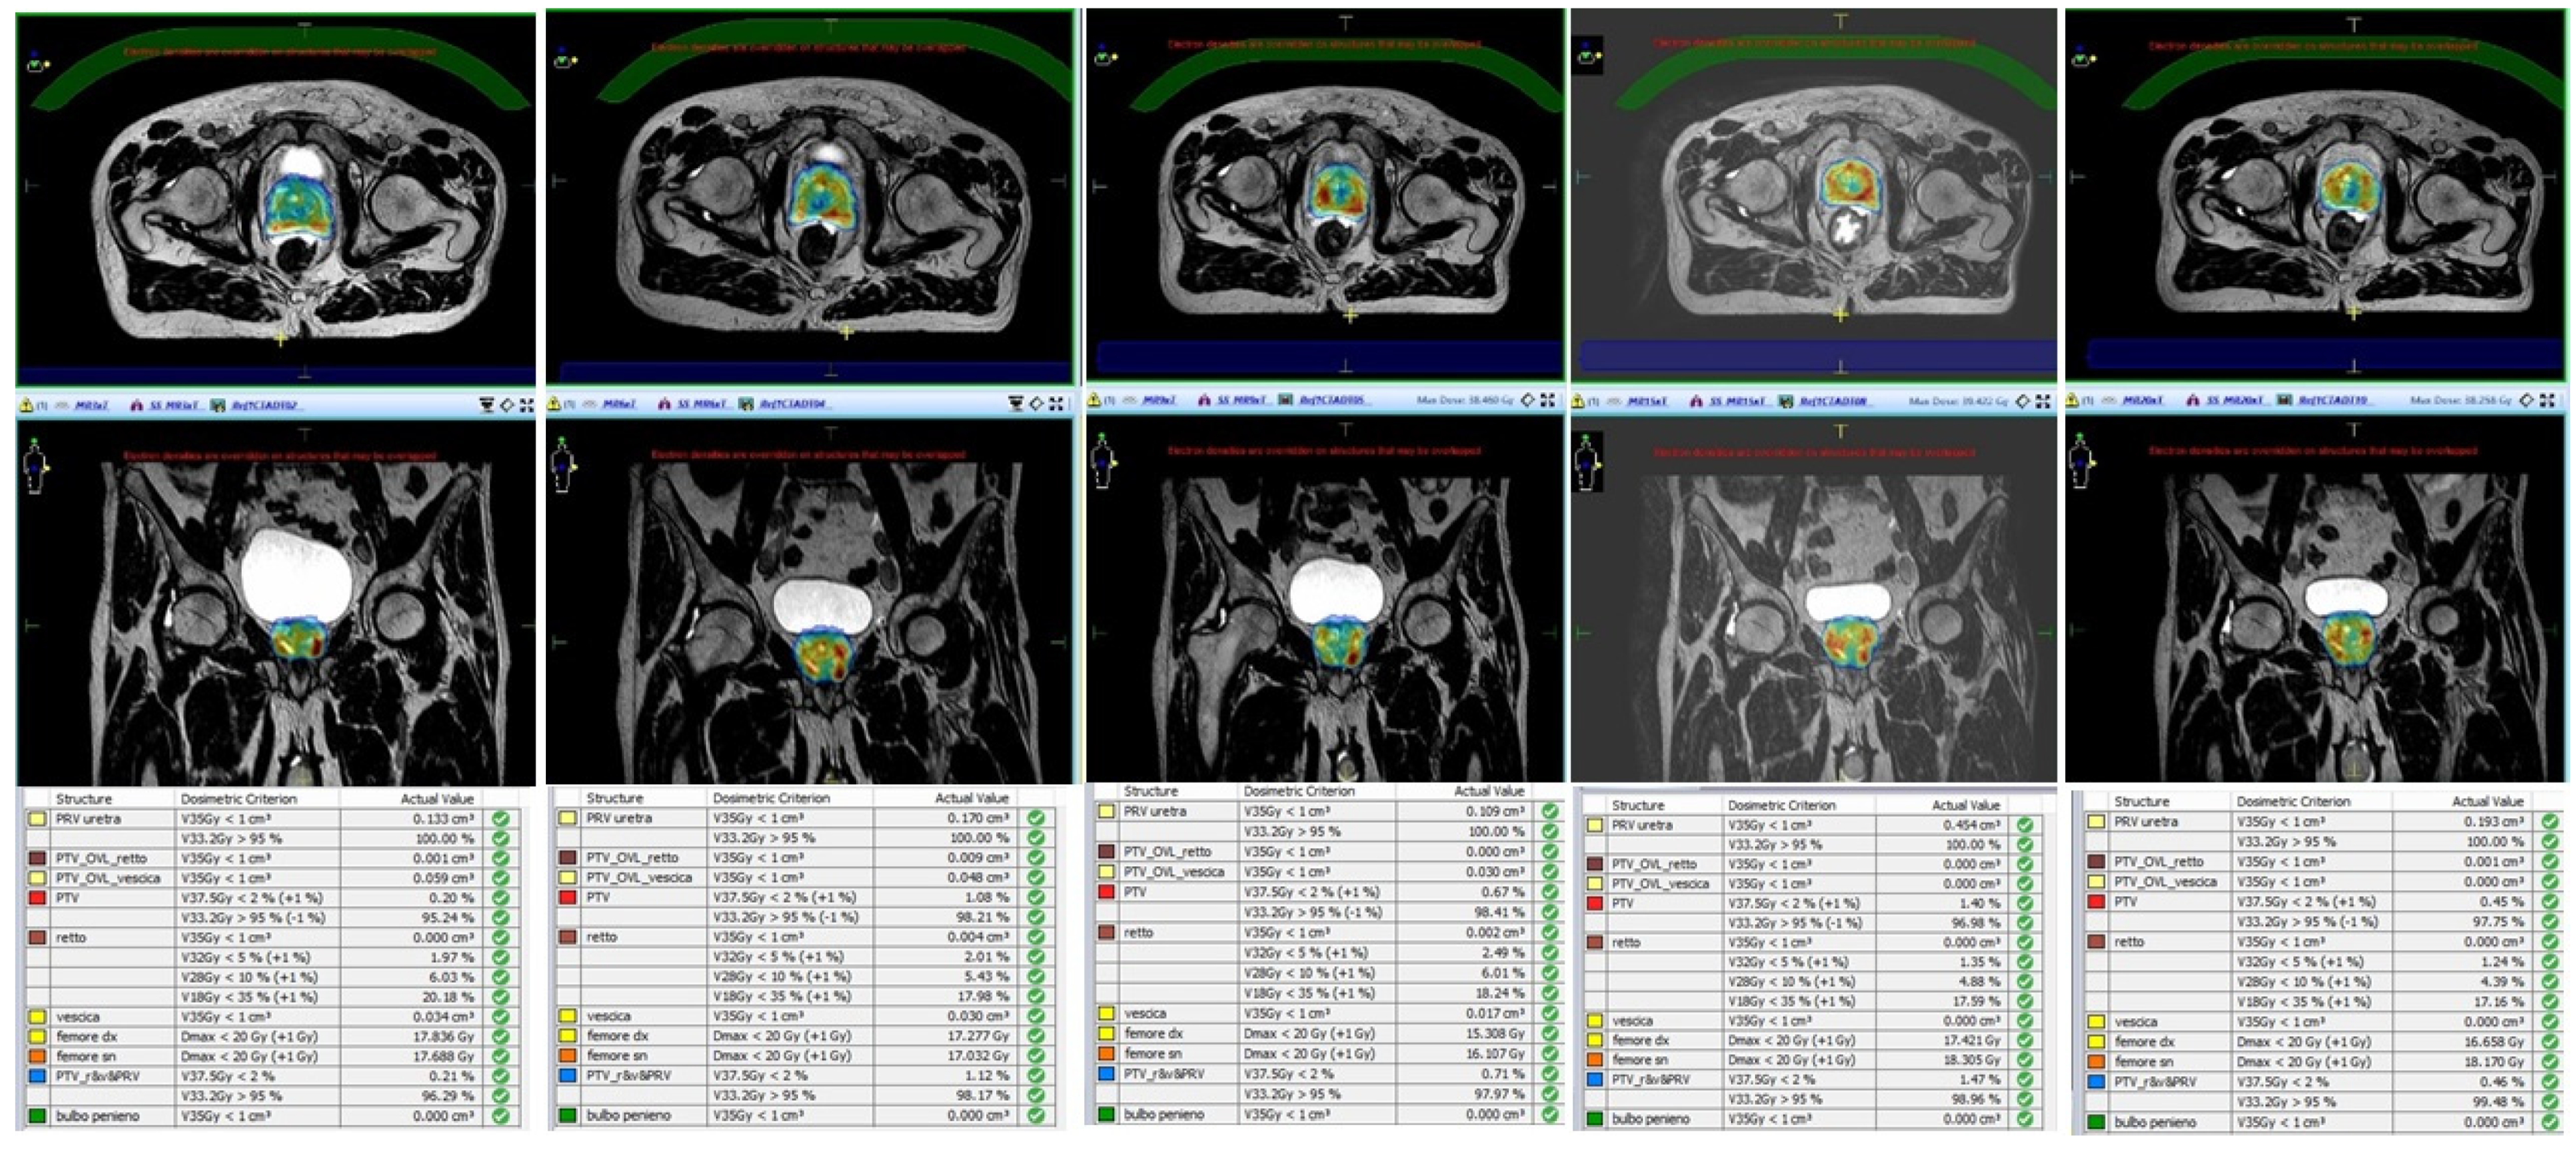

- Alongi, F.; Rigo, M.; Figlia, V.; Cuccia, F.; Giaj-Levra, N.; Nicosia, L.; Ricchetti, F.; Sicignano, G.; De Simone, A.; Naccarato, S.; et al. 1.5 T MR-guided and daily adapted SBRT for prostate cancer: Feasibility, preliminary clinical tolerability, quality of life and patient-reported outcomes during treatment. Radiat. Oncol. 2020, 15, 1–9. [Google Scholar] [CrossRef]

- Nicosia, L.; Sicignano, G.; Rigo, M.; Figlia, V.; Cuccia, F.; De Simone, A.; Giaj-Levra, N.; Mazzola, R.; Naccarato, S.; Ricchetti, F.; et al. Daily dosimetric variation between image-guided volumetric modulated arc radiotherapy and MR-guided daily adaptive radiotherapy for prostate cancer stereotactic body radiotherapy. Acta Oncol. 2021, 60, 215–221. [Google Scholar] [CrossRef] [PubMed]

| Alongi et al. [36] | 20 | Elekta Unity | 35 Gy/5 fractions | Dosimetric analysis and preliminary PROMs report | Hydrogel improves rectal sparing with minimal impact on QoL |

| Cuccia et al. [34] | 20 | Elekta Unity | 35 Gy/5 fractions | Assessment of the impact of rectal spacer on prostate motion | Significant impact on rotational antero-posterior shifts with consequently reduced prostate motion |

| Nicosia et al. [39] | 10 | Elekta Unity | 35 Gy/5 fractions | Dosimetric comparison between MR-guided SBRT and conventional Linacs SBRT | MR-guided SBRT resulted in lower constraint violation rates |